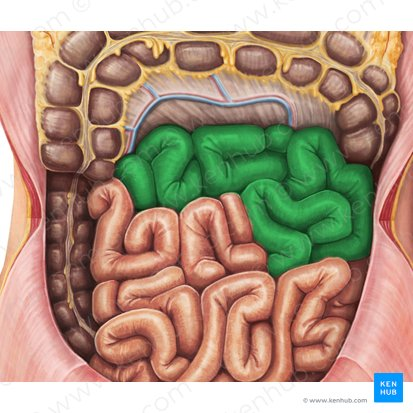

Duodenum

This is the first and shortest segment of the small intestine. It receives partially digested food (known as chyme).

Receives digestive enzymes from the pancreas and bile from the liver and gallbladder through the pancreatic and bile ducts.

Jejunum

This is the middle section of the small intestine, and is characterized by numerous folds and villi, which increase the surface area for nutrient absorption.

Most of the absorption of carbohydrates, lipids, and proteins occurs

Ileum

The final and longest section of the small intestine, which controls the passage of material into the large intestine.

primarily absorbs vitamin B12, bile salts, and any remaining nutrients, and also plays a role in the transport of water and electrolytes.

Jejunum

The middle section of the small intestine, where most of the digestion and absorption of carbohydrates, lipids, and proteins occurs.